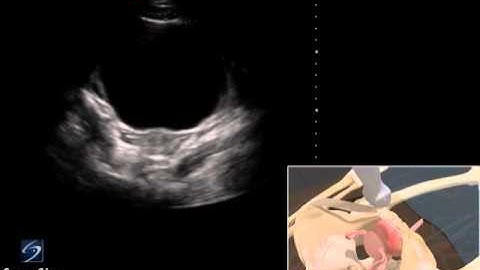

How to assess the pelvic hiatal area using a new 3D ultrasound technique